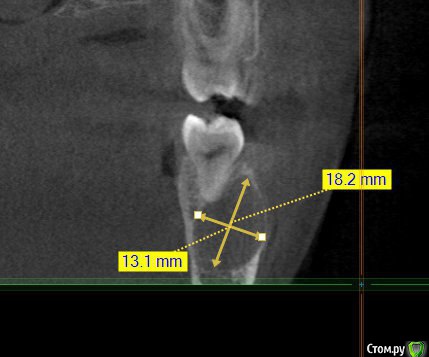

Kovalov Igor Опубликовано 14 июля, 2015 Поделиться Опубликовано 14 июля, 2015 (изменено) Уважаемые коллеги приветствую Вас! Встал вопрос стоит ли трогать фолликулярную кисту или наблюдать?Пациентка моя сестра, фолликулярная киста была случайной находкой, обнаружил ортодонт, отправил в областную больницу г. БелгородаВ детской ЧЛХ отказались, отправили в Харьков, это был 2013 год ещё. Во взрослой ЧЛХ не взялись, по возрасту. В детской члх сделали КТ, снимки и панораму прилагаю.Ps: картина за 2 года стала получше, но КТ сделают позже, есть внеротовой Rg снимок. Дело в том что я живу от сестры более 3000 км., сам бы это дело вскрыл амбулаторно, цистэктомия, графт+мембрана если гноя не будет... либо под йодоформом. Но вопрос стоит ли? и как по протоколу, каков Ваш план лечения? Депульпировать ли зубы 45-46? Изменено 14 июля, 2015 пользователем Kovalov Igor Ссылка на комментарий

Kovalov Igor Опубликовано 14 июля, 2015 Автор Поделиться Опубликовано 14 июля, 2015 вот Rg свежий. Вроде граница фолликулярной кисты уменьшилась.Как сделают КТ поделюсь тут... Буду признателен за ответы! Ссылка на комментарий

kriokov Опубликовано 14 июля, 2015 Поделиться Опубликовано 14 июля, 2015 Игорь' это не фолликулярная киста. Никакие зубы не депульпируйте. Сделате кт повторно. Сравните с прежними.скорее всего киста от ранее находившегося в дуге молочного зуба. После повторного кт можно будет сказать поточнее. Ну и с тактикой определиться. Сейчас что Вашу сестру беспокоит (жалобы)? 2 Ссылка на комментарий

Kovalov Igor Опубликовано 14 июля, 2015 Автор Поделиться Опубликовано 14 июля, 2015 Игорь' это не фолликулярная киста. Никакие зубы не депульпируйте. Сделате кт повторно. Сравните с прежними.скорее всего киста от ранее находившегося в дуге молочного зуба. После повторного кт можно будет сказать поточнее. Ну и с тактикой определиться. Сейчас что Вашу сестру беспокоит (жалобы)?А как отличит по КТ фоликулярную кисту от обычной кисты?Жалоб никаких не было, в 4 года ей лечили временный зуб в этой области. Возможно это и есть отголоски. Повторное КТ уже порекомендовал ей. Сделают, выложу тут.Благодарю Вас за ответ! Ссылка на комментарий

Alexey Doc Опубликовано 14 июля, 2015 Поделиться Опубликовано 14 июля, 2015 Фолликулярная киста связана с ( зачатком) зуба А как отличит по КТ фоликулярную кисту от обычной кисты?Жалоб никаких не было, в 4 года ей лечили временный зуб в этой области. Возможно это и есть отголоски. Повторное КТ уже порекомендовал ей. Сделают, выложу тут.Благодарю Вас за ответ! Фолликулярная киста связана с коронкой прорезывающегося или ретинированного зуба. А это скорее всего резидуальная 3 Ссылка на комментарий